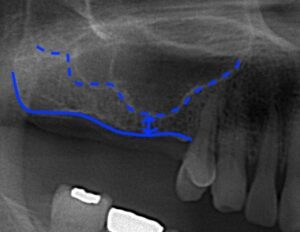

しかしレントゲンを撮影しますと矢印部分しか骨の長さがなく

点線部分がサイナスになります。これは5mm以上持ち上げないと

いけませんのでサイナスリフトが必要になります。